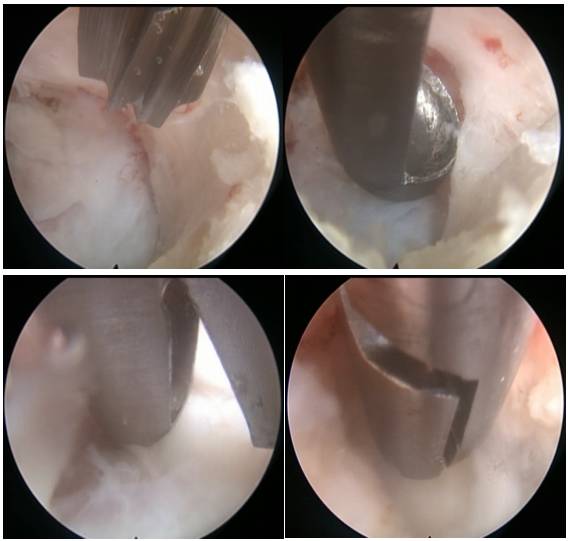

手术经过:全麻后患者取俯卧位,C臂透视定位下L1/2中线左侧旁开1cm纵行切开皮肤约8mm,扩张导杆穿刺L1/2左侧椎板间黄韧带,置入工作鞘,退出导芯,内镜下暴露L1/2左侧上下椎板及黄韧带,磨钻磨除左侧L2椎板上缘部分骨质,镜下椎板咬钳咬除黄韧带后,显露病灶,呈囊性,囊壁质地较韧,蓝钳切开囊壁后囊内见胶冻样粘液组织涌出,内镜下抓钳逐块移除囊壁内白色类结晶物,并尽可能分块切除囊壁,达大部切除。内镜下仔细止血、检查创面,见硬膜完整,局部受压解除后局部脑脊液液性张力下恢复膨隆,镜下可见脊膜搏动(图3)

图3. 脊柱内镜下经椎板间入路切除腰椎关节滑膜囊肿。